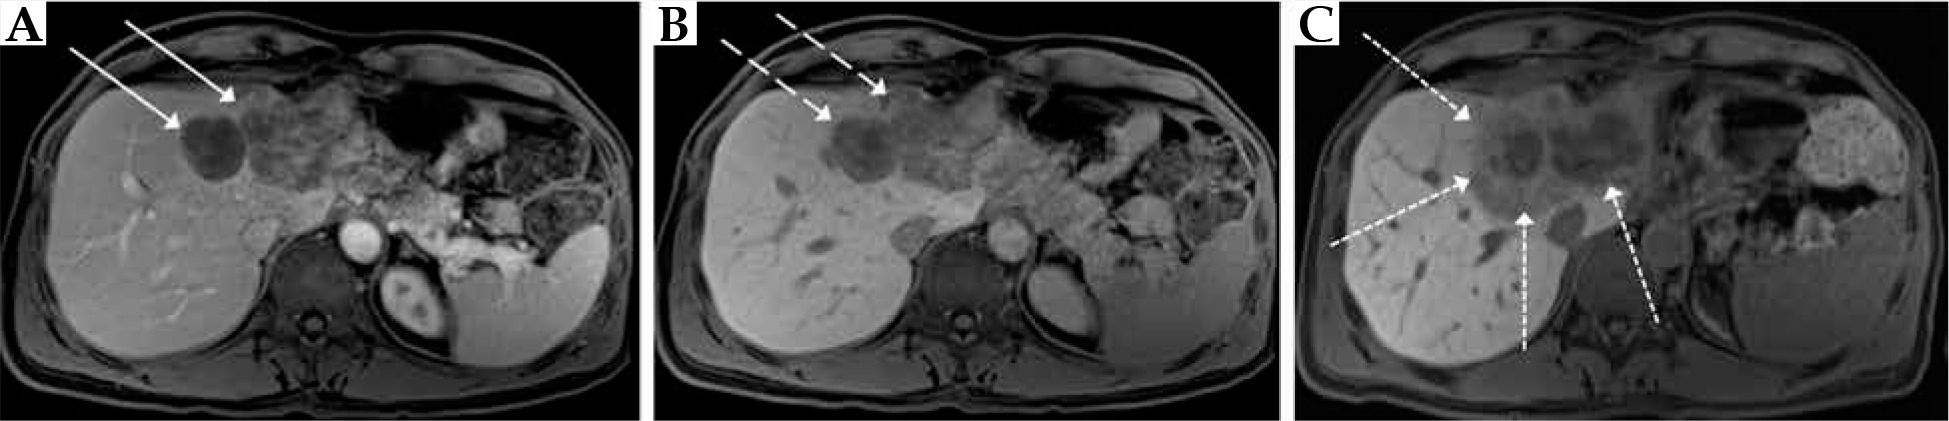

Fig. 1

Pre- (A, B) and 60-days post-interventional MRI (C) in a patient with colorectal liver metastases in the left liver lobe after treatment with irinotecan transarterial chemoembolization and CT-guided high-dose-rate brachytherapy. A) Fat-saturated T1 transverse sequence after Gd-EOB-DTPA-injection in the portal venous phase with an inhomogeneous enhancement of the liver metastases in liver segments II and IVa (arrows); B) Fat-saturated T1 transverse sequence with missing Gd-EOB-DTPA-retention in the liver metastases (dashed arrows); C) Fat-saturated T1 transverse sequence with missing Gd-EOB-DTPA-retention in the liver metastases as well as perifocally corresponding to irradiation volume (dotted arrows)